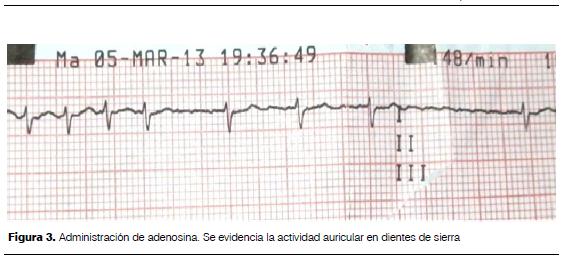

Se realizó adenosina no retomando ritmo sinusal, objetivando como se ve en la figura 3 espaciamiento de los complejos QRS y la presencia de ondas en dientes de sierra características del flutter auricular, se realizó entonces cardioversión eléctrica sincronizada con 5 J, efectiva, revirtiendo a ritmo sinusal (figura 4).

La administración de adenosina produce bloqueo del nodo aurículo-ventricular no permanente permitiendo identificar pacientes con arritmias en los que la onda P está enmascarada por el QRS o la onda T(13); la no respuesta a la dosis inicial y la evidencia de ondas en dientes de sierra inmediato y fugaz a su administración permitió confirmar el diagnóstico de flutter auricular, procediendo entonces a realizar la cardioversión eléctrica sincronizada, tratamiento óptimo en el período posnatal(13,14).